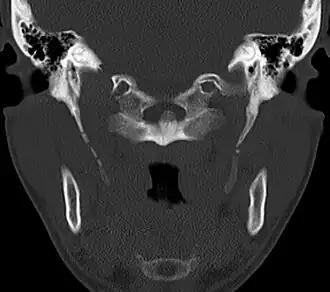

CT scan, coronal section showing bilateral extended styloid process and stylohyoid ligament ossification (incidental finding) -